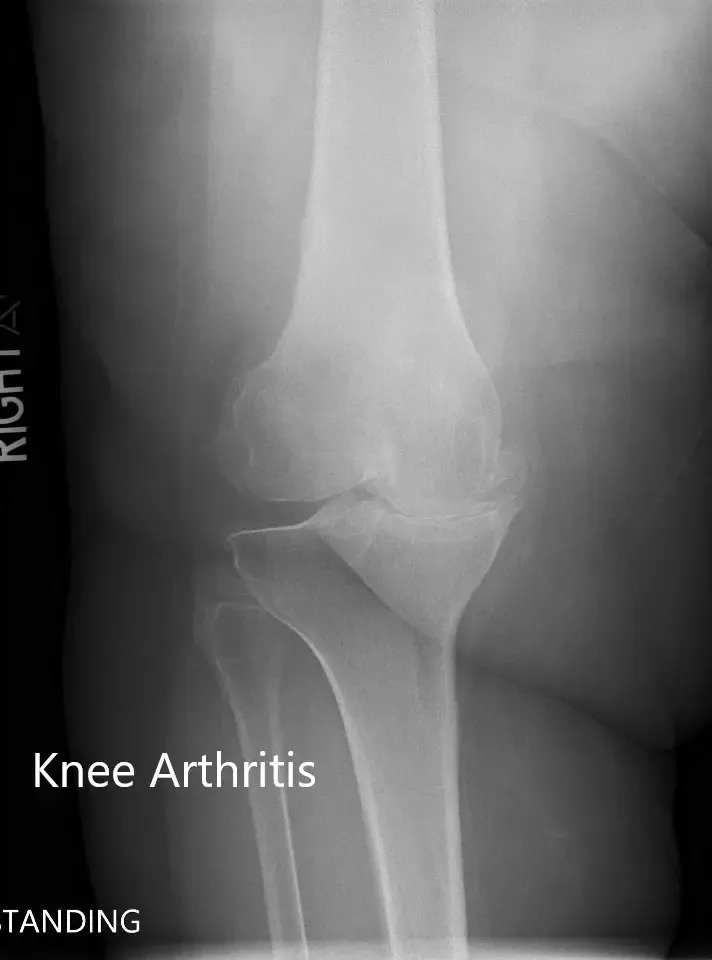

No había déficit neurológico distal. Los pulsos distales de las extremidades eran palpables y comparables. Las imágenes revelaron una osteoartritis tricompartmental severa de la rodilla derecha. Opciones que discutieron extensamente con ella, incluyendo métodos quirúrgicos y no quirúrgicos. Le dieron la opción de un reemplazo de rodilla personalizado adecuado. Ella aceptó seguir adelante.

Radiografía preoperatoria de la rodilla derecha que muestra visión AP y lateral.